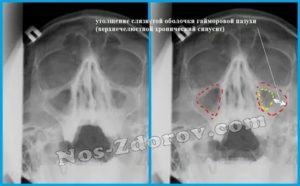

Гиперплазию эпителия можно заметить только на рентгеновских снимках. При подозрении на утолщение врач выдает направление на рентген, который позволит заметить даже минимальное увеличение эпителиального слоя в виде затемнения. Рентген также показывает наличие и уровень жидкости в синусах, а по ее расположению можно определить степень воспаления.

Для постановления диагноза используют риноскопию, в ходе которой специалист может обнаружить отечность слизистых оболочек, бледность определенных участков, повреждение сосудов. Если присутствуют симптомы, характерные для хронического гайморита, необходим рентген носовых пазух. Только на рентгеновских снимках можно заметить начальные стадии образований и пристеночный отек.

В больной зоне при пальпации можно обнаружить характерный для кисты «хруст пергамента». На рентгене образование на фоне светлой пазухи выглядит как затемнение кругловатой формы. Подобными клиническими признаками характеризуются кисты как левой, так и правой пазухи.